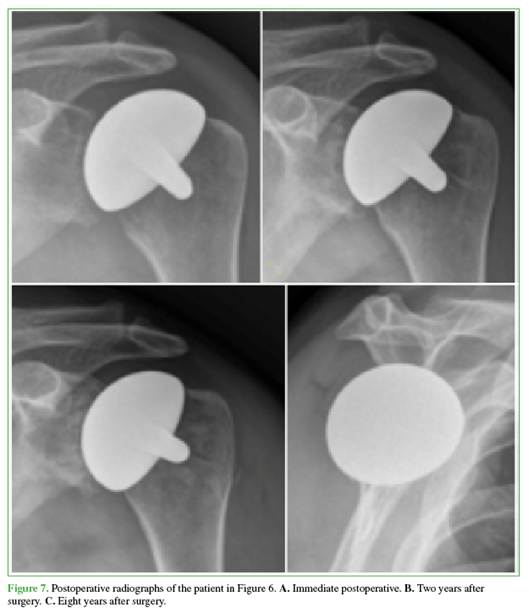

Active range of motion also improved. Forward elevation increased from 70.0° ± 25.0° preoperatively to 135.3° ± 24.8° at 12 months. Abduction rose from 57.2° ± 5.8° to 103.4° ± 9.0°. External rotation with the arm adducted improved from 25.1° ± 2.5° to 55.0° ± 4.6°. Internal rotation, graded on an ordinal scale, improved from 1.48 ± 0.50 to 4.04 ± 0.72 over the same period (Figures 6 and 7).

Radiographic findings: preoperatively, all 25 shoulders had Samilson–Prieto12 grade-3 osteoarthritis (loss of joint space, cysts, and osteophytes) (Figures 6 and 7).

Seven had asymmetric glenoid wear (Walch type B1 in 4 and B2 in 313). In addition, seven shoulders had moderate subluxation and one had severe subluxation. Postoperatively, subluxation resolved in 22 shoulders and persisted mildly in three. Mean glenohumeral joint space increased from 1.2 mm (range, 0–3) to 3.4 mm (range, 1–5) (Figure 8).